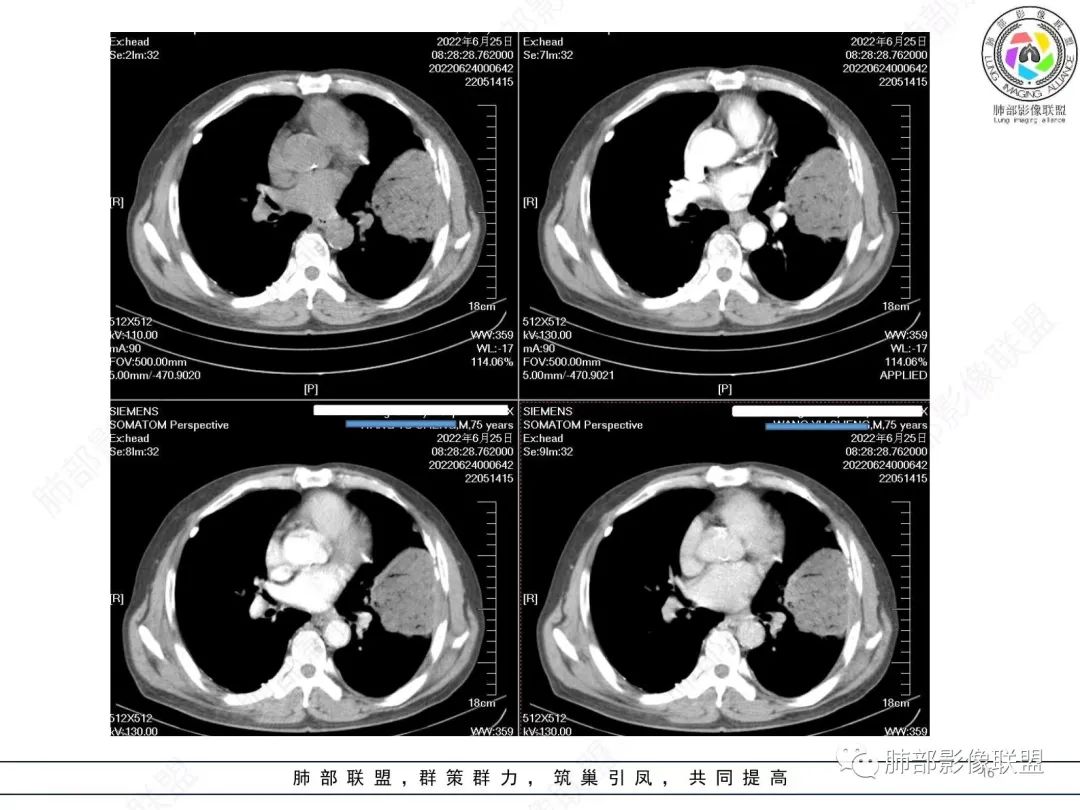

大肿块、表面光滑但深分叶,肺门侧支气管堵塞

我一开始诊断恶性,定在淋巴瘤,还觉得信心满满

回头看,内部支气管近端其实不连续,伴随肺动脉不存在

这两点就不符合

还有如果从支气管的特点考虑黏膜相关性淋巴瘤,其整体应该是边缘不清楚为主,肺炎样为主。

原发性肺肉瘤样癌(PSC)一组临床罕见的肺部肿瘤,属于上皮细胞源性肿瘤,仅占肺部恶性肿瘤的0.3%~4.7%。为含有肉瘤形态细胞或肉瘤样分化的非小细胞肺癌,癌成分多为鳞癌或腺癌,肉瘤成分最常见的是纤维肉瘤。

肺肉瘤样癌的CT表现主要特点:

1)部位:周围型或中央型软组织肿块,以周围型为多见,且肿瘤多位于肺上叶。如本例:该肿瘤位于左肺上叶。

2)大小及形态:由于本病恶性程度高,早期症状不明显,发现时肿块均较大。如本例病变巨大。

3)肿块边界和边缘:多较清楚,呈圆形、类圆形,且由于肿块生长速度不均匀,可见分叶,毛刺少见。有报道肿块周围毛玻璃影是多形性癌特征表现。